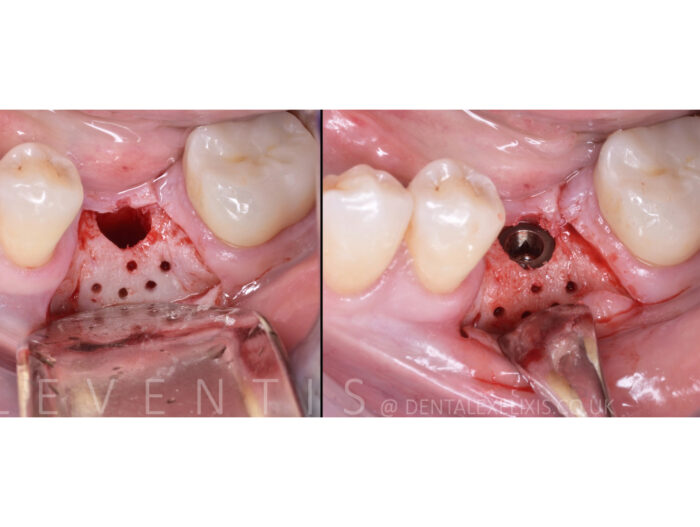

Działa jako szkielet, który umożliwia tworzenie nowej kości. Do stabilizacji możemy użyć pinów lub śrub do osteosyntezy.

Struktura gąbki chroni obszar przed naciskami zewnętrznymi, które występują podczas mowy i żucia.

- Możliwość wstępnego dopasowania do ubytku.